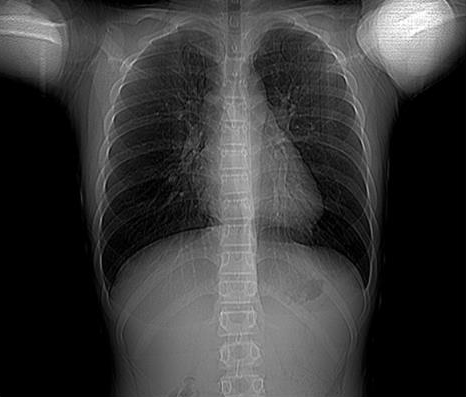

WIth the events happening around the world due to the global pandemic, I came up with this idea to build a covid detector based on XRAY images. Because SARS-CoV-2 attacks the epithelial cells lining the lungs, it can be detected from posterioranterior view of the lungs. With limited testing kits, this solution can prove to be favorable and also give results in an instant.

Classify if person has COVID or not and also identifies the regions in lungs it has spread

Trained a ML model to classify xray images of lungs as covid positive or negative and exposed web sevice using flask

Built the end-to-end solution. The output also shows why the ML model predicts it is covid positive or negative. Highlights on Xray images are shown and how it resulted in the prediction.